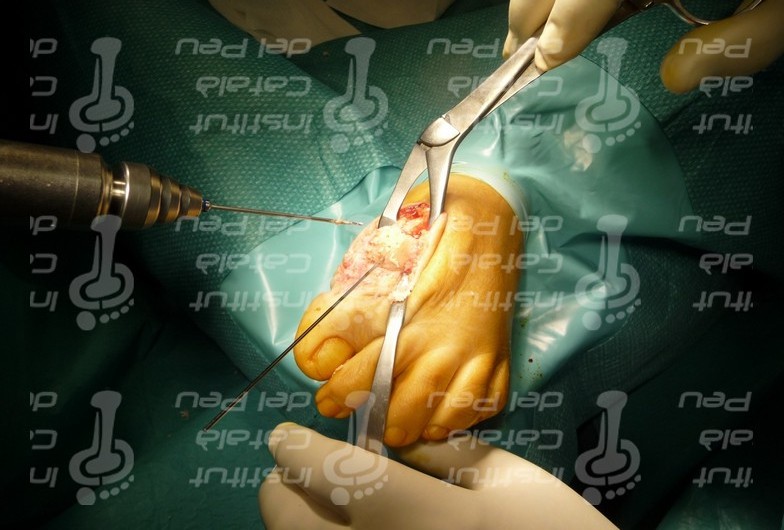

Para la realización de la artrodesis lo más importante es la preparación de las superficies articulares y la posición en la que artrodesaremos la AMTF (Figs. 3 y 4). La posición correcta para la artrodesis (estando el pie en carga) es con el eje de la falange paralelo al suelo, una angulación en el plano sagital de 20-25º de la AMTF en flexión dorsal, 5-10º de valgo en el plano transversal y con una rotación del dedo neutra (nos ayudamos de la posición de la uña, que ha de quedar completamente paralela al suelo). Para la preparación de las superficies articulares se suelen utilizar fresas cóncavo-convexas, fresando y eliminando el cartílago articular para que la fusión de la articulación sea lo más completa y estable posible. Una vez fresada la cabeza del metatarsiano y la base de la falange proximal debemos mantener la articulación en la posición correcta y escoger el material de osteosíntesis. En caso de escoger tornillos canulados para fijar la artrodesis, introducimos dos agujas de Kirschner (AK) que aguantarán la AMTF y nos sirven para brocar y hacer el agujero guía para introducir el tornillo, poniendo los tornillos cruzados entre sí (Figs. 5 y 6). En caso de escoger fijar la artrodesis con placa, sistema biomecánicamente más estable ( Fig.7), también utilizamos las AK para aguantar la AMTF, colocando la placa en el dorso de la AMTF y brocando para introducir los tornillos que aguanten la placa. Repetimos el procedimiento para fijar la articulación con grapas de memoria, poniendo una grapa en la parte medial de la AMTF y otra en la cara dorsal.

Preparación de la superficíe articular de la base de la falange proximal del primer metatarsiano. Eliminación del cartílago articular mediante fresado.